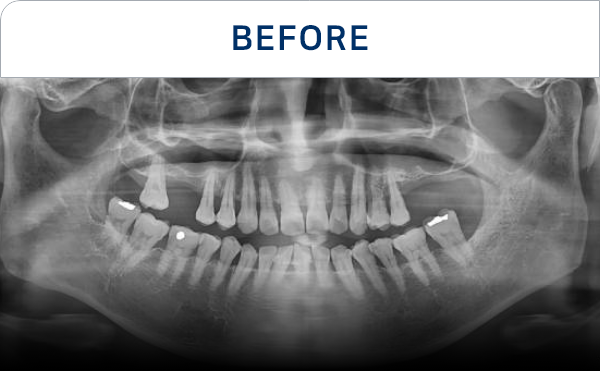

种植牙是在精准诊断与治疗计划的基础上,

通过多个步骤进行的治疗方式

会根据患者的口腔状况, 分阶段安全推进

通过CT, 扫描等数字设

备拍摄后,

进行精密分析

考虑骨骼状态与神经位置,

制定种植位置与手术计划